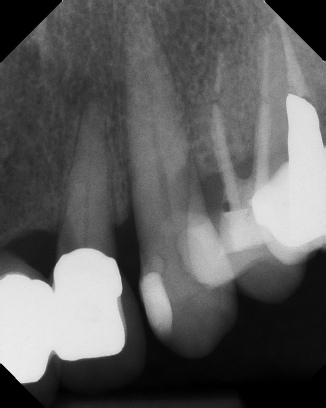

COMPLICATED ANATOMY LARGE LESIONS CALCIFIED CANALS PERFORATION / RESORPTION SEPARATED INSTRUMENTS SURGICAL CASES RETREATMENT / pOST REMOVAL OPEN APICES ACCESS THRU CROWNS Root Canal Case Portfolio

6 mos.